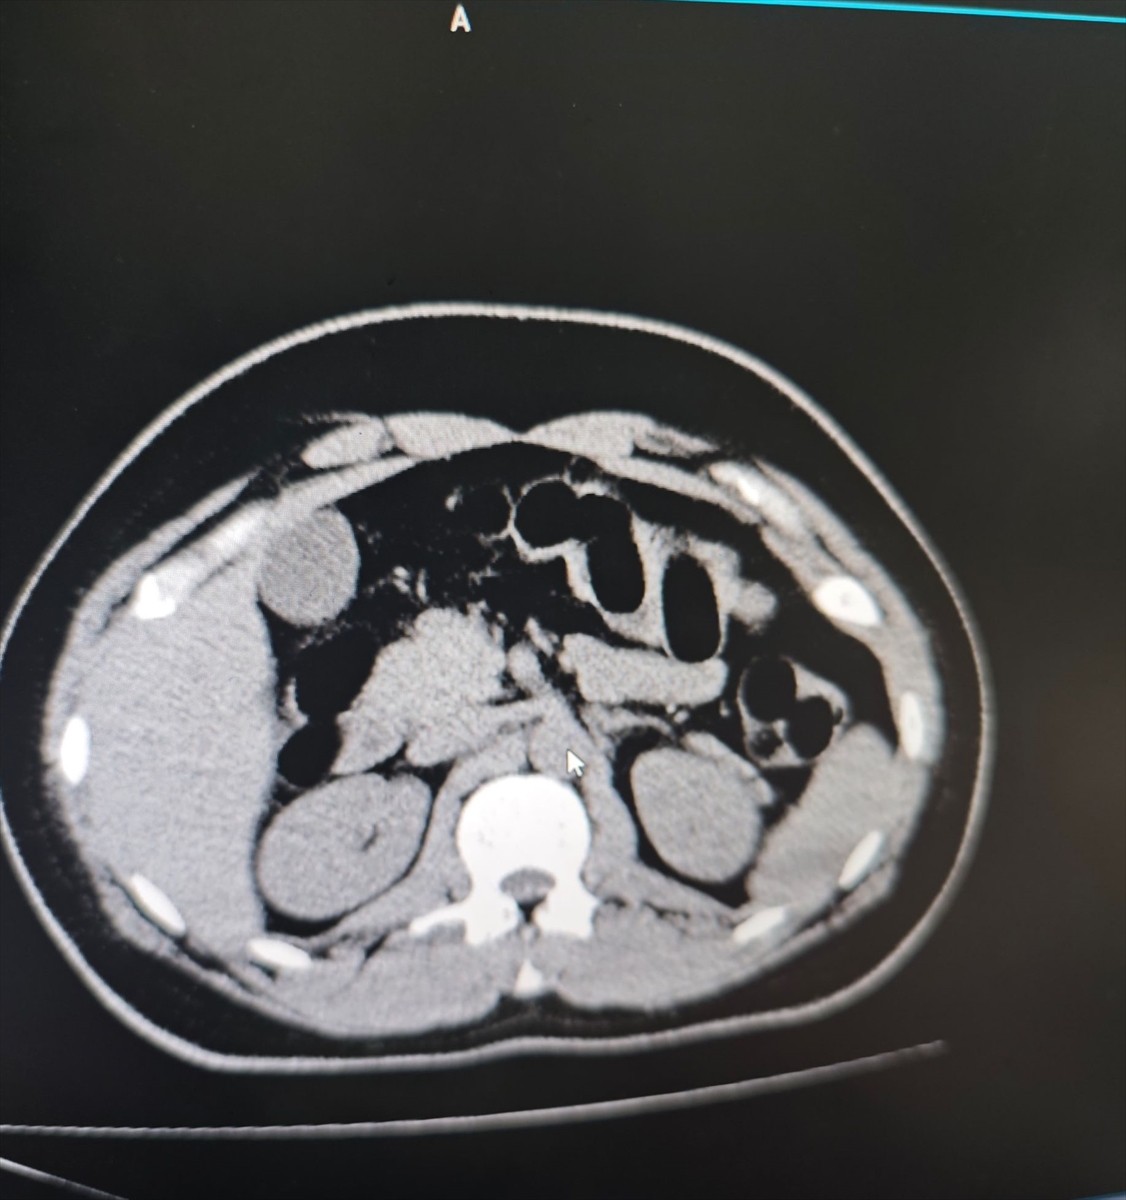

25 Aralık'ta, şüphelinin bulunduğu şehirlerarası yolcu otobüsü, ekiplerce kent girişinde oluşturulan kontrol noktasında durduruldu. Gözaltına alınan S.S., hastaneye götürülerek yapılan iç beden muayenesi ve tomografi görüntülemesi sonrasında midesinde uyuşturucu taşıdığı belirlendi.

Şüphelinin midesinden 84 kapsül içinde toplam 842 gram eroin ele geçirildi. S.S., çıkarıldığı hakimlikçe uyuşturucu ve uyarıcı madde ticareti suçundan tutuklandı.